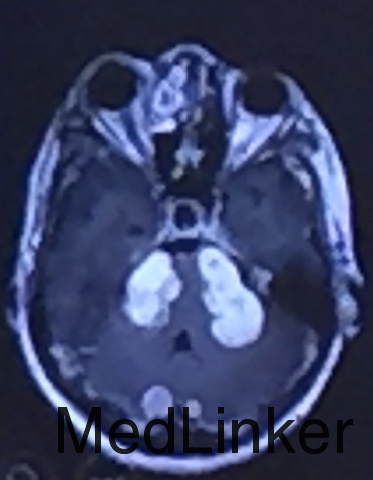

查体:双侧听力减退,四肢肌力、肌张力正常,病理征(-)。 辅助检查:神经系统MRI如下图所示:符合神经纤维瘤病NF2型。